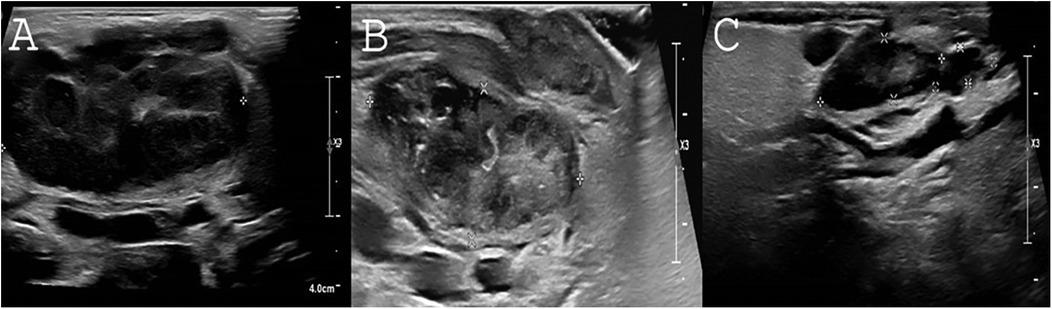

Figure 3. Response of lymphadenopathy to rapamycin treatment. (A) Severely enlarged bilateral submandibular lymph nodes as viewed by US upon P2's first examination. Length of right submandibular lymph node is measured 4.36 cm. (B) Two months following rapamycin treatment. A marked decrease of the right submandibular lymph node can be seen (3.6 × 1.1 × 1.4 cm) without abscess formation. (C) Following 1.5 years of rapamycin treatment, continuing decrease in the size of the right submandibular lymphadenopathy is noted (2.1 × 0.6 × 1 × 0.41 cm).

For immunomodulatory treatment, P2 was treated with rapamycin, initiated at a dose of 2 mg/m²/day and maintained at the same dosage. The target therapeutic levels were set at 5–15 ng/ml. Rapamycin levels were first monitored one week after initiation, along with a blood lipid profile and complete blood count (CBC). Given normal results, a follow-up blood draw was performed two weeks later. Subsequently, rapamycin levels, CBC, chemistry panel with lipids, and immunoglobulin levels were monitored at each pediatric daycare visit for IVIG administration. Additionally, EBV and CMV PCR screening was conducted every three months, though routine BK virus screening was not performed. Rapamycin treatment is ongoing, with no adverse events observed. Both patients are currently alive and well under treatment, with no further recurrent sinopulmonary infections. Before rapamycin treatment, P2 had severely enlarged bilateral submandibular lymph nodes, with the right submandibular lymph node measuring 4.36 cm. After 2 and 18 months of rapamycin treatment, the size of the right submandibular lymph node significantly decreased to 3.6 × 1.1 × 1.4 cm and 2.1 × 0.6 × 0.41 cm, respectively. No abscess formation was noted. The sonographic resolution of lymphadenopathy in P2 under rapamycin treatment is depicted in Figures 3A–C.